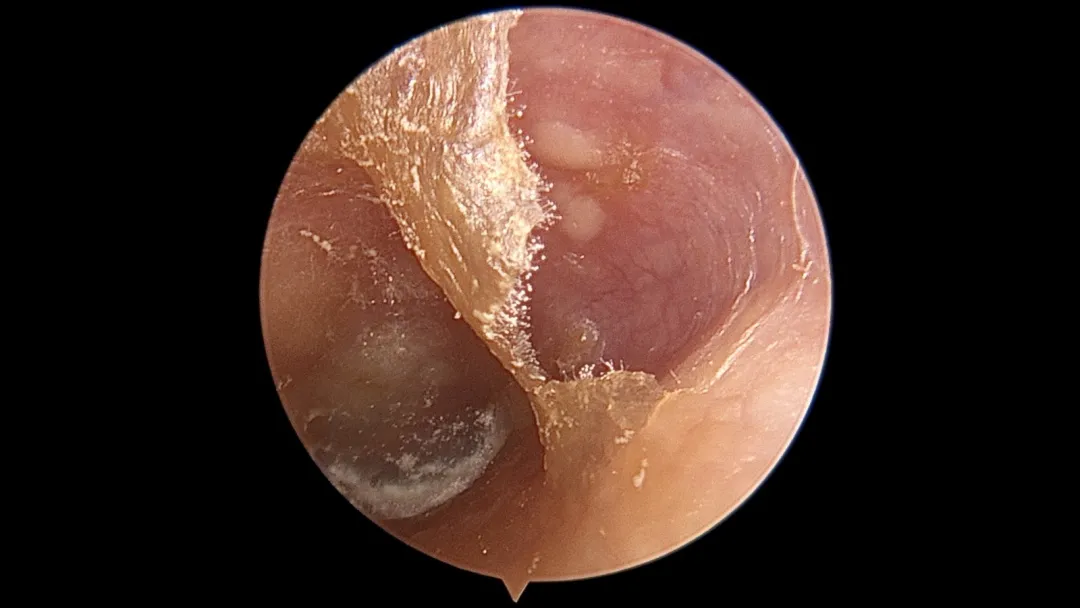

专业的说法叫:霉菌性外耳道炎,也就是真菌感染。

致病的真菌种类很多,常见的有以曲霉菌、念珠菌、青霉菌及毛霉菌。

程度轻的能看到一些霉丝和霉点,严重的可能会有一些脓性分泌物。

除此之外,如果痂皮或分泌物阻塞外耳道,或覆盖在鼓膜表面,人可能会出现听力减退和耳鸣。

这时候,在你看不到的地方,耳朵可能就已经变成了这副“病入膏肓”的样子——